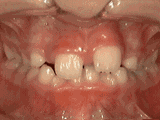

Phase I

Patient's parents were concerned about both aesthetics and the health of the erupting permanent teeth when they brought him to the orthodontist at age eight. The lower front teeth were crowded and they touched the palate, and the upper front teeth were extremely displaced from their normal positions. After 20 months of Phase I treatment with an expander and partial braces, patient's appearance and dental function was vastly improved.